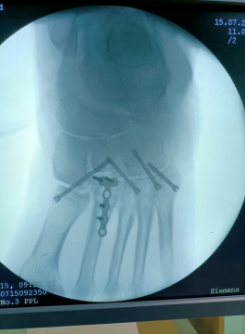

64岁的张大爷不小心摔倒跌伤后,发觉左脚脚踝处非常疼痛不能动弹,他连忙叫家人送来我院治疗。经诊断,张大爷左跗跖关节骨折脱位。

得知老人焦虑的状态后,骨伤科主任周建全及时与患者沟通交流,安抚好患者的情绪,并为患者制定了最佳诊疗方案——“骨折有限切开复位内固定手术”,整个治疗过程痛苦少、费用低、恢复快。

周建全说"骨折有限切开复位内固定手术”从外面来看,仅是一个非常小的切口,在足跟部这个敏感部位能做到小创伤,有着传统手术方法绝对无法比拟的优势,不仅能促进骨折完全复位,减少用药剂量,更能缩短住院时间,有效减轻患者的痛苦。

科室设备先进,拥有西门子C臂X光机、床旁X光机、storz关节镜、Arthroscope System关节镜、骨科多功能手术床、脊柱手术器械、关节置换器械、骨科牵引床、各种物理作业康复设备等,进口西门子、高清晰移动C臂X光机能满足骨科各种有创治疗需要,使创伤最小各种复位更精确、内固定更安全可靠,同时科室备有两套进口关节镜,常年开展膝关节镜治疗膝、肩关节内疾病,且有各种康复治疗设备,充分满足骨科患者治疗的需求。